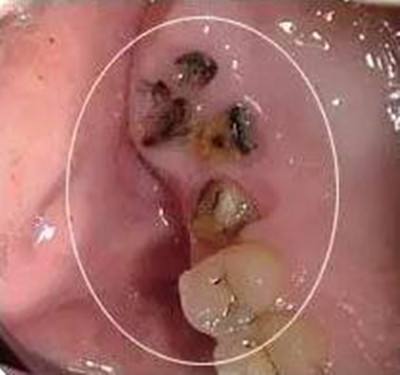

5、残根残冠。针对没有保留价值的残根残冠,建议提前拔除,以免孕期发生根尖炎;针对有保留价值,可以修复的残根残冠,要做好根管治疗,如果时间充裕,孕前做好冠修复,如果时间比较紧张,可以等生完孩子再做冠修复。